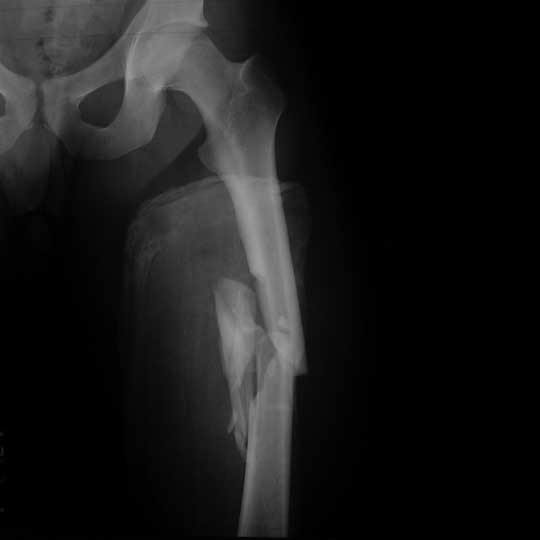

Comminuted Fracture

This is your classic 'well that's broken' fracture. It's defined as a fracture where the bone is in more than two fragments. Let's have a look below...

Comminuted fracture of the femur

[Image source](https://eorif.com/femoral-shaft-fracture-s72309a-